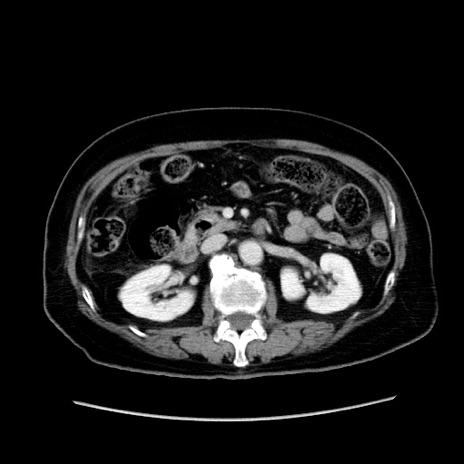

冠状断像

【症例】80歳代女性

【主訴】下腹部痛

【現病歴】約8時間前より下腹部痛の出現あり、救急外来受診。

【既往歴】両側付属器切除

【身体所見】意識清明、下腹部正中に手術痕あり、その部位に一致して圧痛と反跳痛あり。腸蠕動音は亢進。

【データ】WBC 9300、CRP 0.15